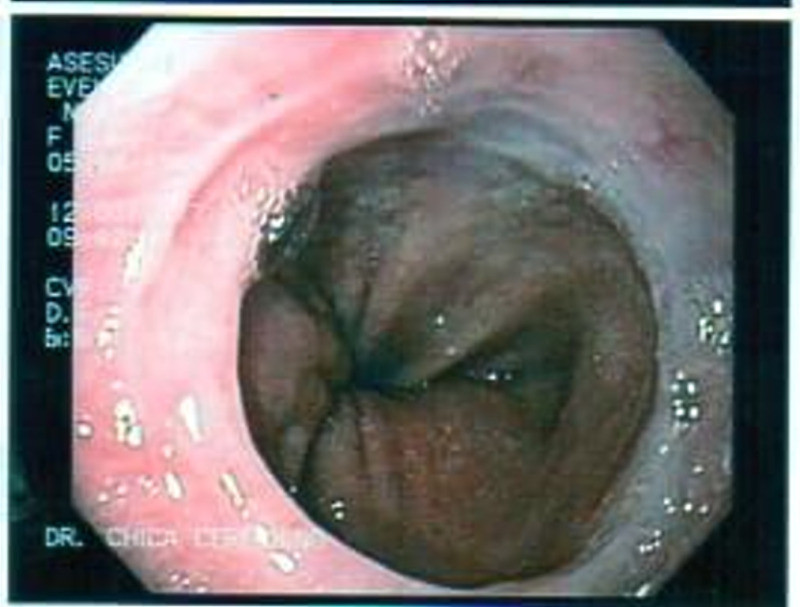

Cálculo gigante por coledocoliatisis